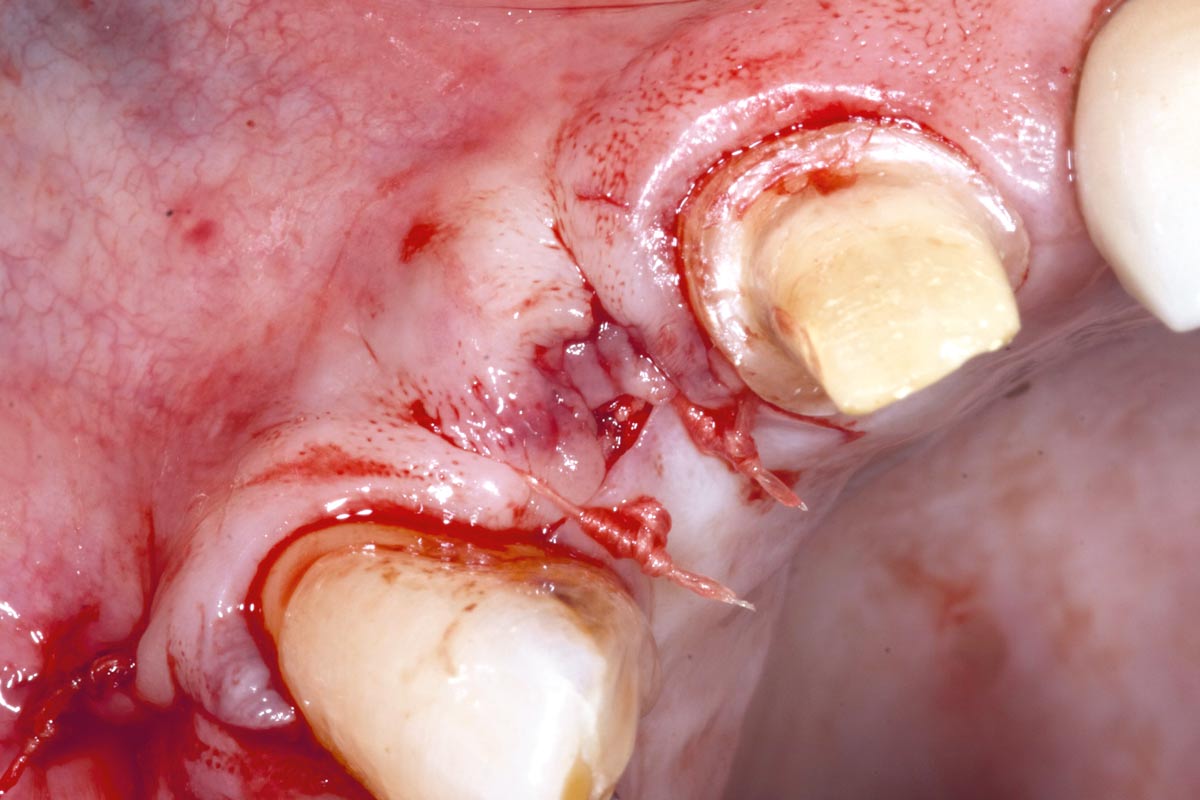

4/19 - Site after extractionBone augementation with maxresorb® - Dr. R. Cutts